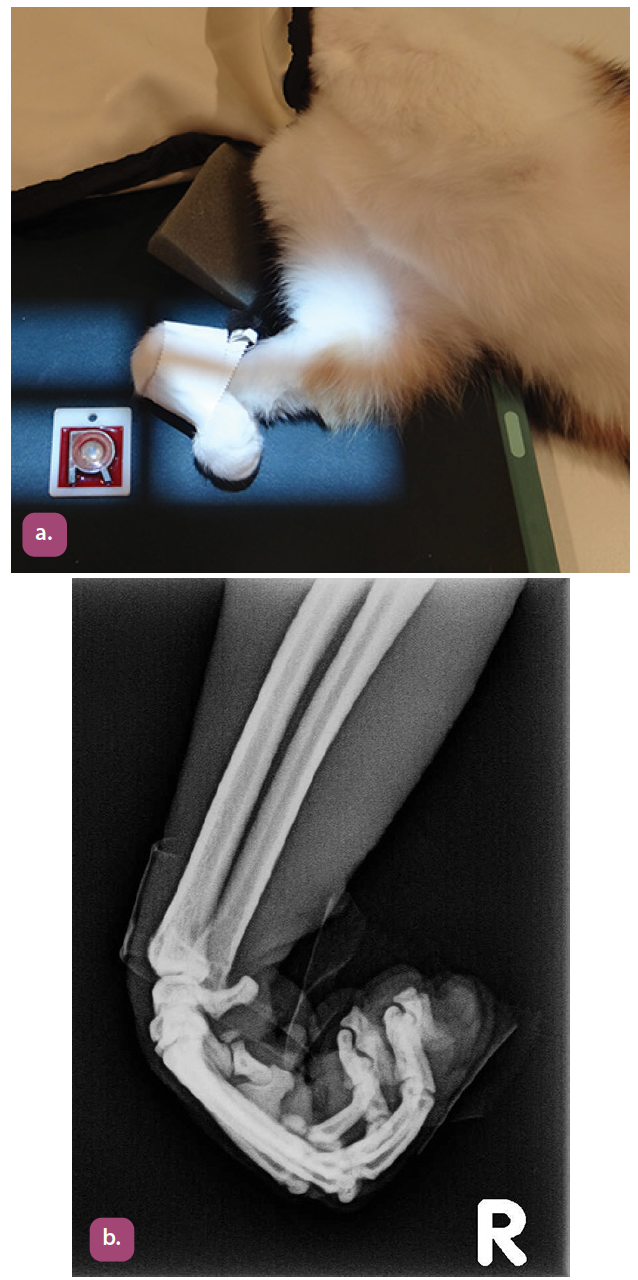

mediolateral projection of the carpus

flexed mediolateral projection of the carpus